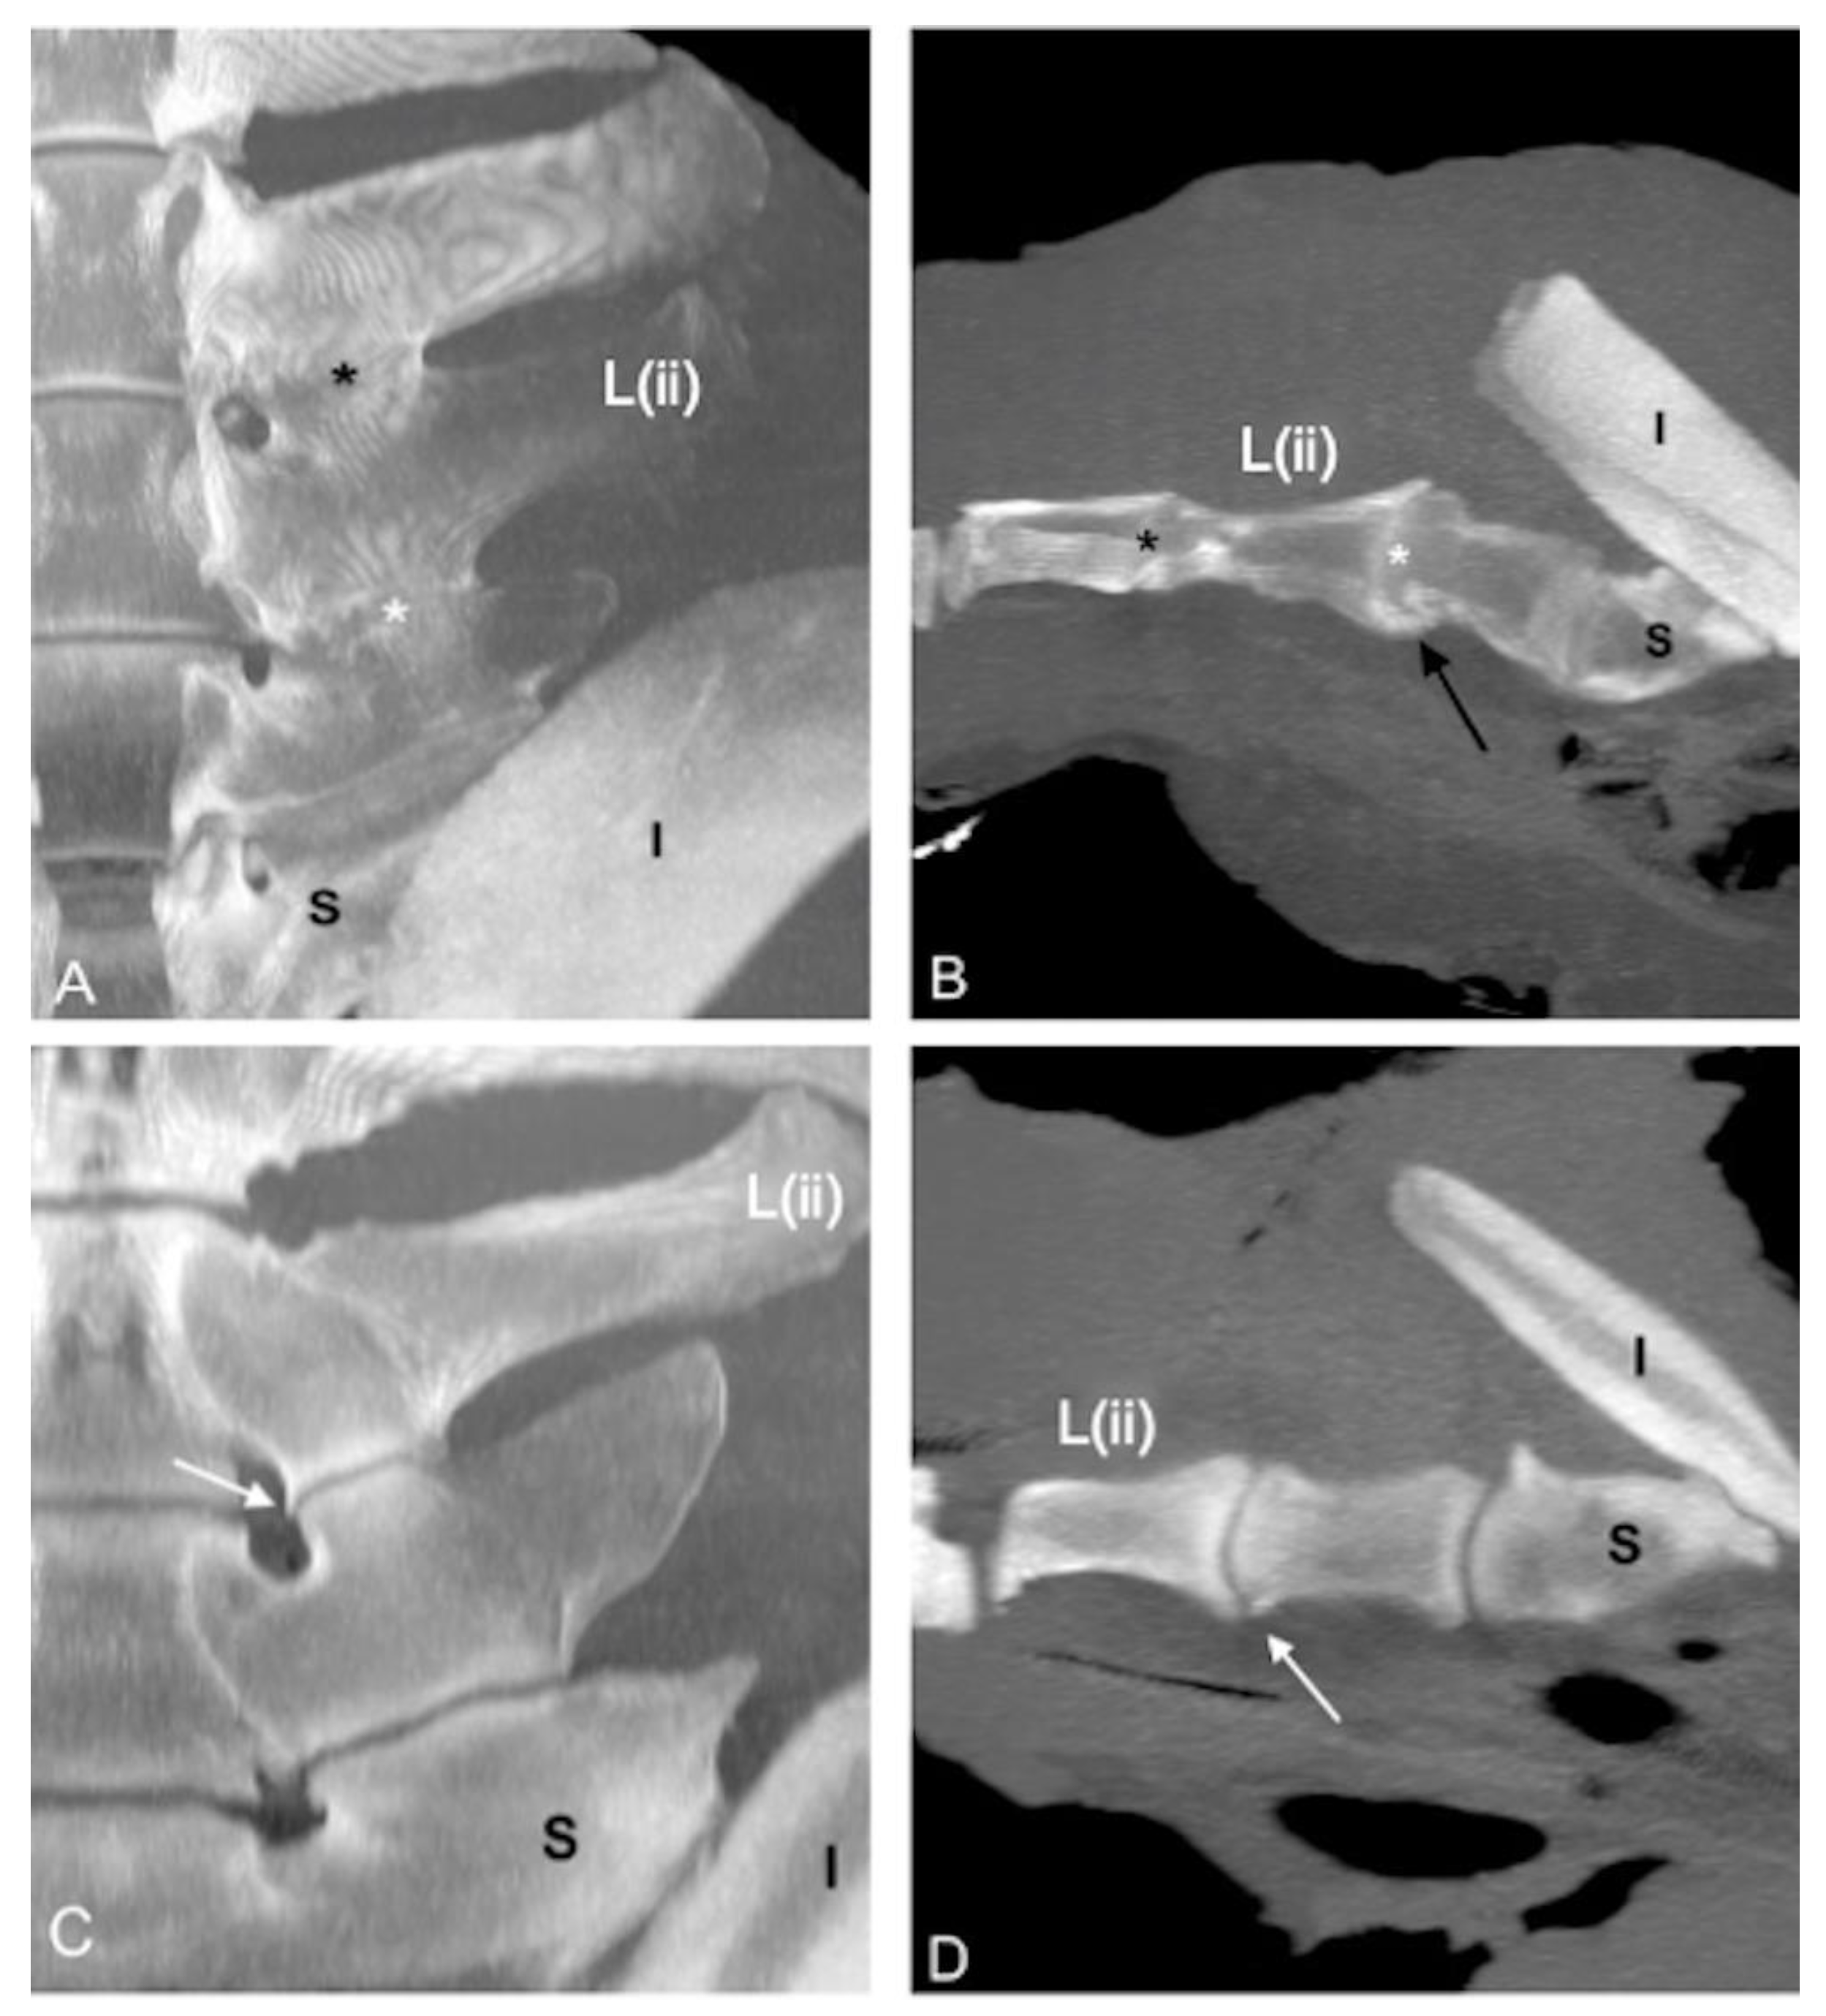

A partial intervertebral joint fusion (dorsal fusion) of L(ii)-L(i) was found in nine specimens (22.5%) (Figure 8).

The partial intervertebral joint fusion of L(ii)-L(i) was detected in concomitance with the bilateral fusion of L(ii)-L(i) ITJs in five specimens (62.5%) and unilateral fusion of L(ii)-L(i) ITJs (on the right side) in one specimen (12.5%). In one spine (12.5%), a partial intervertebral joint fusion of L(ii)-L(i) was detected in association with a fusion of L(iii)-L(ii) ITJs, a fusion of L(ii)-L(i) ITJs, and ankylosis of L(iii)-L(ii) APJs; in another spine (12.5%), the partial intervertebral joint fusion of L(ii)-L(i) was found together with the fusion of L(ii)-L(i) ITJs and ankylosed L(iii)-L(ii) APJs.

Figure 8. Sagittal (A,C,E); cranial is toward the left) and dorsal (B,D,F); cranial is toward the top) multiplanar reconstruction CT images of the lumbosacroiliac specimens 19, 25, and 33 using maximum intensity projection. (A,C,E) Note the marked narrowing of the L(ii)-L(i) intervertebral discs space (white arrows) with no visible disc space dorsally (dorsal fusion) in comparison with the L(iii)-L(ii) ones, associated with partial fusion of the respective spinous processes (SPs) in specimens 19 and 29. (B,D,F) The L(ii)-L(i) intervertebral disc space is not seen on the ventral aspect (black arrows) in concomitance with bilateral L(ii)-L(i) intertransverse joints (ITJs) fusion in all 3 specimens. L(iii): third to most caudal lumbar vertebra; L(ii): second to most caudal lumbar vertebra; L(i): most caudal lumbar vertebra.